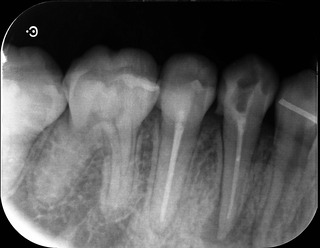

レントゲン。

赤丸の部分が根尖部分の透過像。黒くなっていると思います。

5番と同じく根尖までキレイに根充材は入っていますが‥

こちらは根充後のレントゲン。

心なしか初診時の写真の時より、透過像が小さくなっているような気がします。